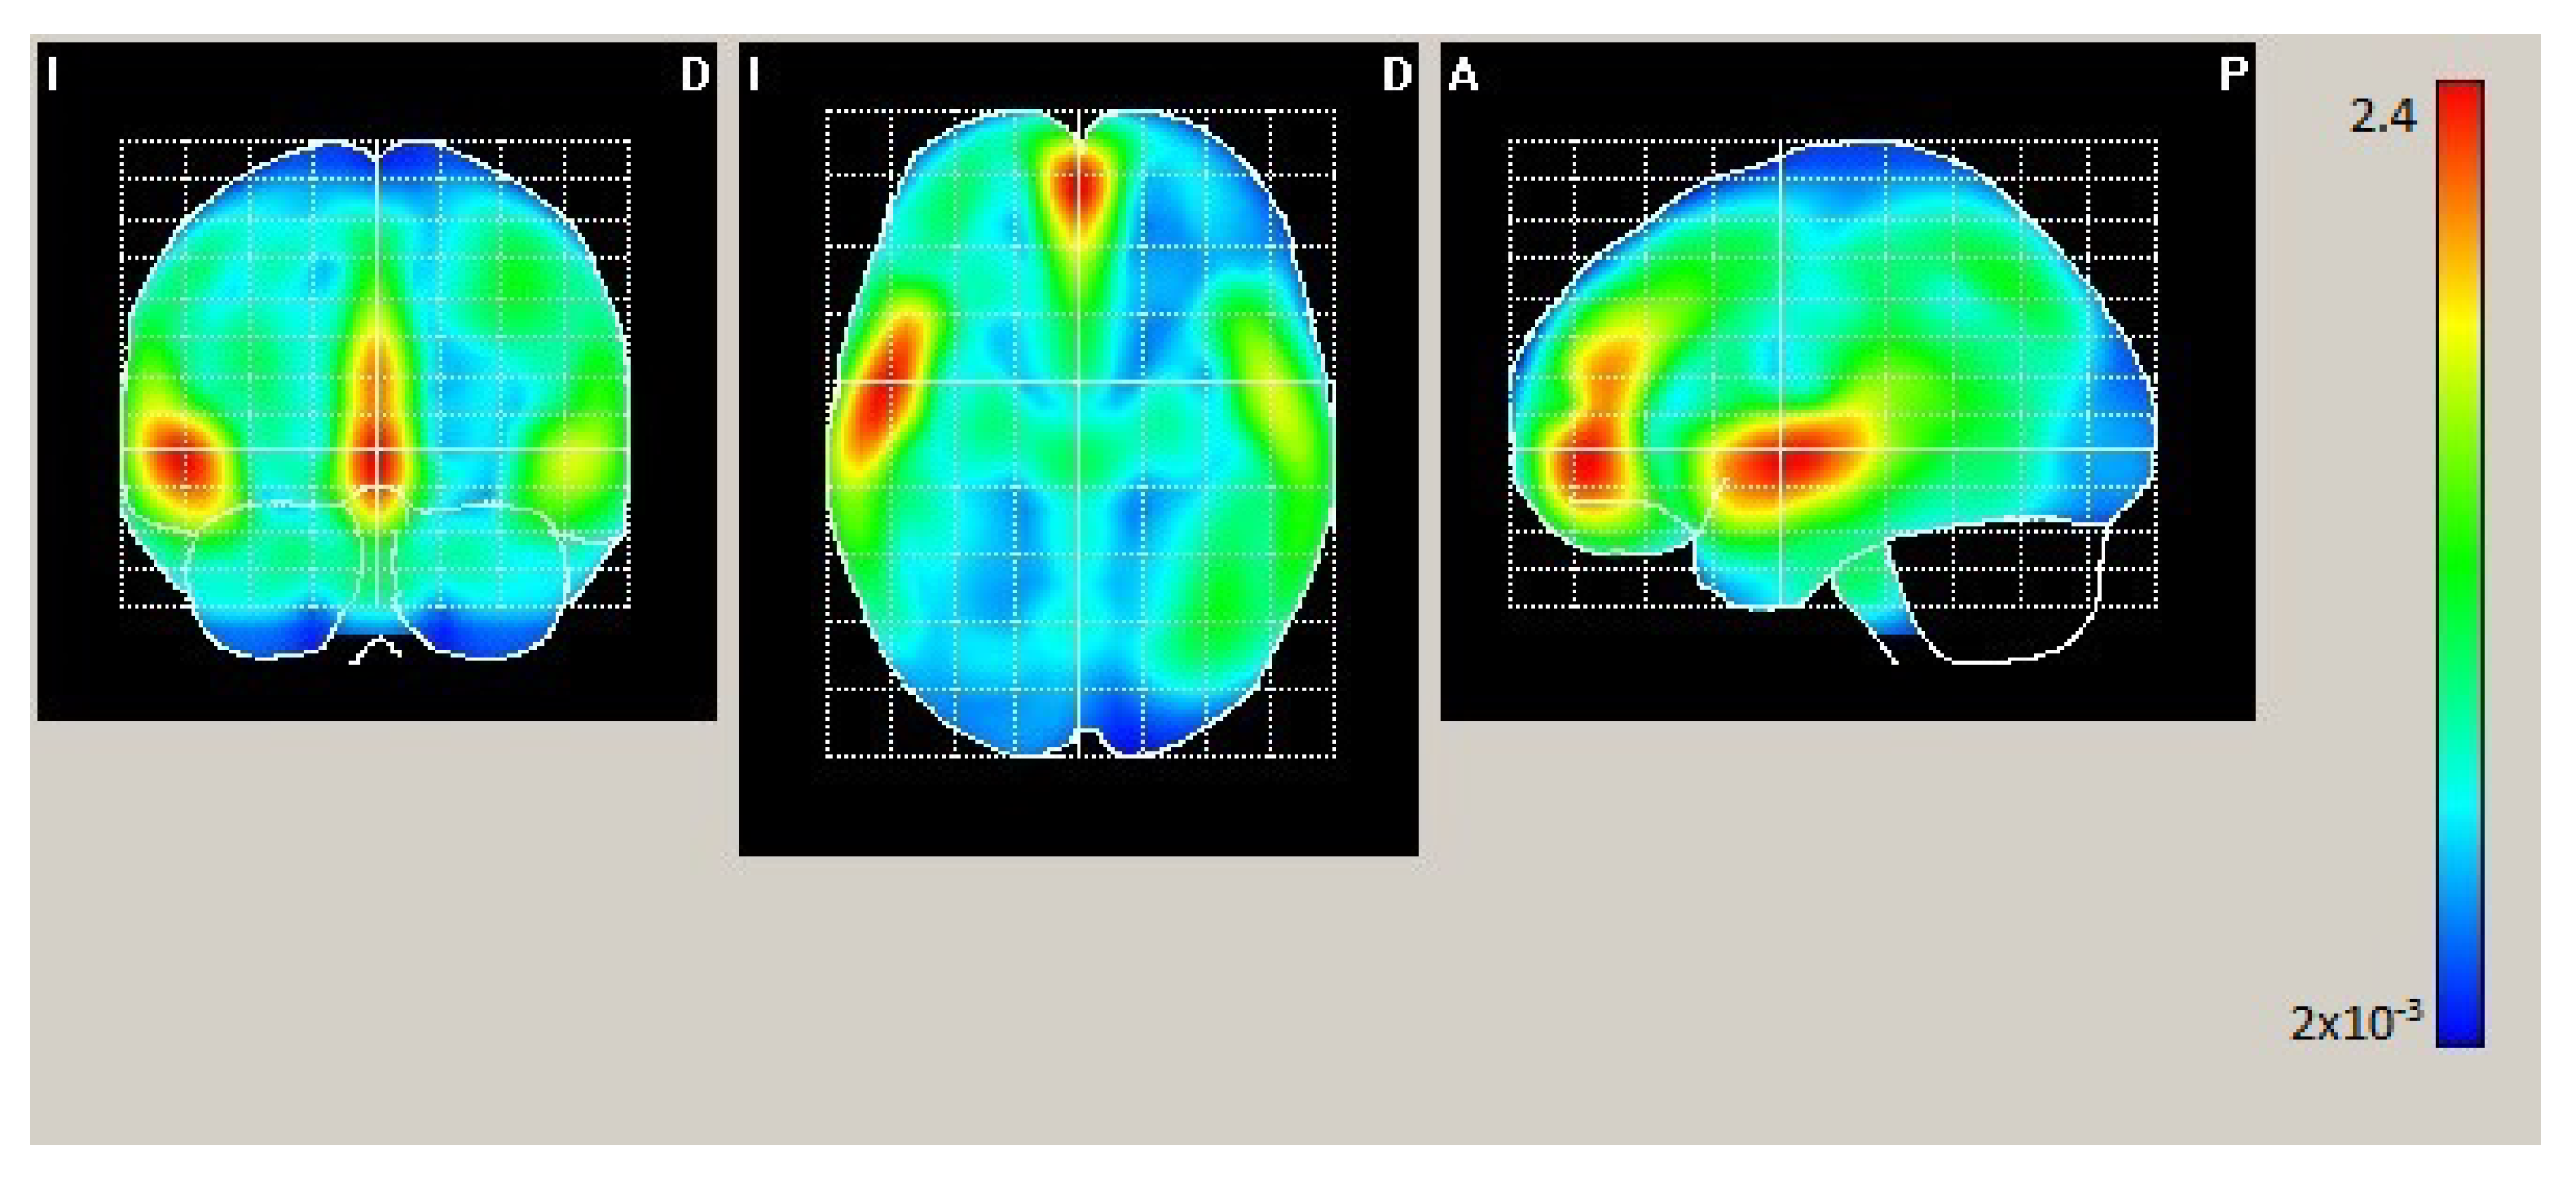

In Condition 2 (hearing-impaired participants and only visual stimulation), as shown in Figure 3 and Table 3, maximum statistically significant activation was found in the bilateral middle frontal orbitofrontal, left superior temporal lobe, bilateral superior frontal gyrus, left cingulum, and insula areas.

Figure 3.

Mean electrical maps for Condition 2 (hearing-impaired participants, visual stimulation). Maximal intensity projection areas are displayed in yellow/red color. SPMs were computed based on a voxel-by-voxel Hotelling T2 test against zero.

Table 3.

Condition 2, with the same columns as Table 2.

Condition 2 (hearing-impaired participants with only visual stimulation) showed similar stimulated areas to Condition 1—superior temporal lobe, bilateral frontal orbitofrontal, and cingulum—but also the right superior temporal gyrus, where the main peaks appeared, which has been identified as a region for multisensory integration [59,60], and the medial temporal gyrus, which is associated with visual and auditory processing [6]. The insula also showed an important peak activation. The insula works both as a nerve center and an integrator between sensory systems. It also works during the perception of affective sounds [61]. Therefore, it concerns emotional processing, translating affective auditory signals into subjective emotions [60]. Finally, it is involved in audiovisual integration tasks [62].

This result is coherent with previous experiments with hearing-impaired participants, where these areas were triggered with high intensity when watching a muted video [63].